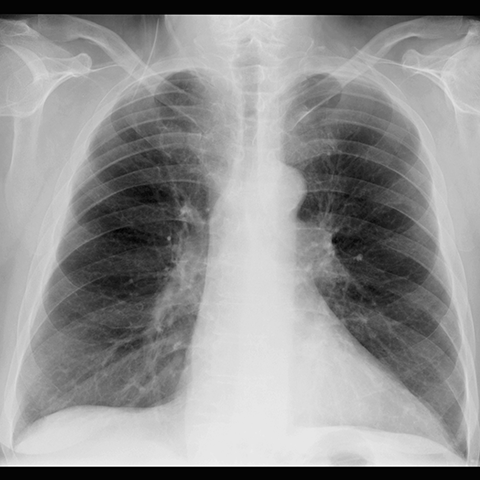

Subtle LLL Retrocardiac Opacity (CXR) [1 of 2]